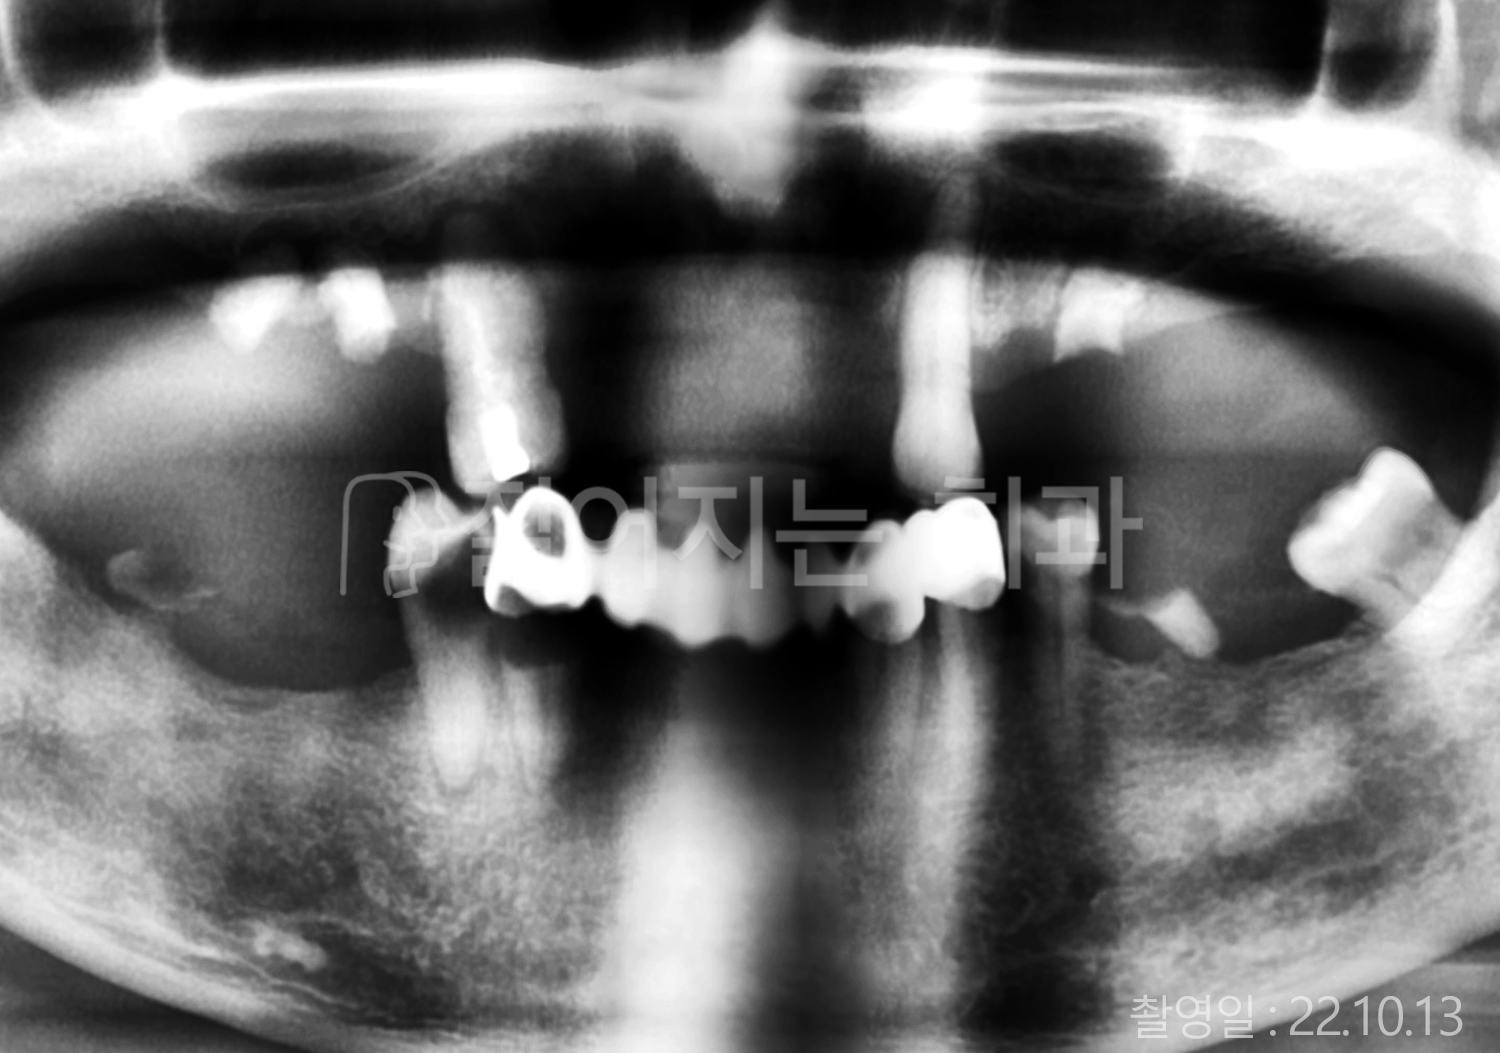

• 40대 전체치아 10개 이상 임플란트